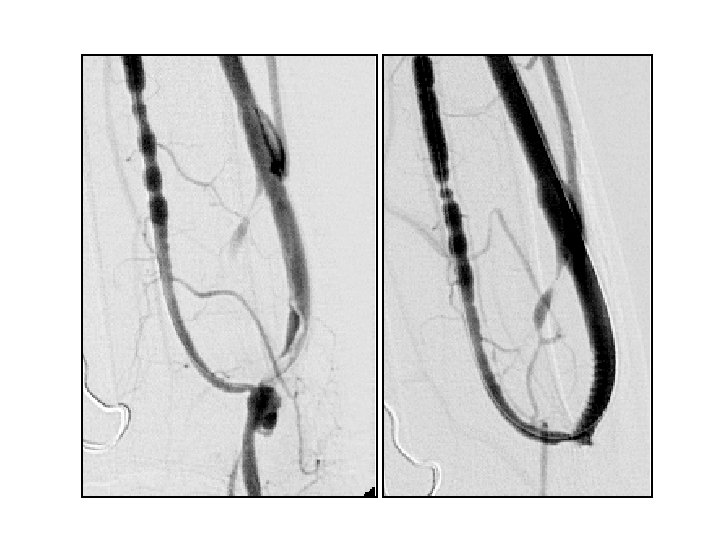

damarla ilişkili lokal komplikasyonlar • Flebit • Venöz tromboz • Oklüzyon • Femoral > Juguler • trombolitik tdv / trombektomi / PTA

PTA sırasında oluşan venöz komplikasyonlar

• venöz rüptür (%2, 1 - 20) • akut / gecikmiş rüptür • minimal ekstravazasyon ve küçük hematom → damar duvar bütünlüğünde belirgin bozulma ve masif hematom • venöz diseksiyon

venöz rüptür • • • Manuel kompresyon Balon tamponat Stent yerleştirme Embolizasyon Cerrahi ligasyon